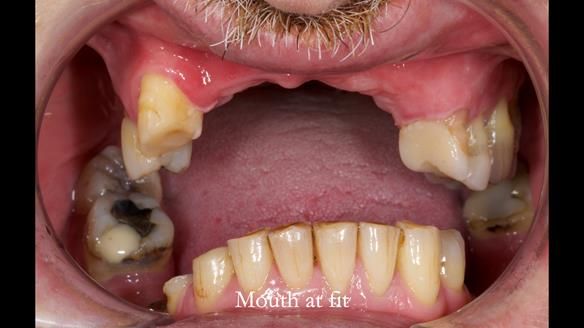

Keith’s case was one of the most challenging and rewarding cases I’ve treated this year. This 64 year old man presented with ill-fitting acrylic partial dentures that lacked stability, retention, and aesthetics. They constantly broke. He had lost the upper front teeth in a road traffic accident in his early 20s. The unopposed teeth had erupted, taking up space. After careful planning, we made a durable, metal-based upper partial denture/splint to address his dental concerns. He loved the outcome.

1. Denture design: A custom cobalt-chromium framework was Scandinavian-designed to maximise stability, protect the remaining teeth, and allow for future additions if needed.

2. Onlay preparations: Composite onlays were fitted for his upper left premolars to repair these teeth and support the new denture.

4. Keith’s outcome: The final denture not only improved Keith’s bite, chewing function, and facial aesthetics but also protected his remaining teeth from further damage.

Keith’s denture incorporated a Duracetal shell clasp on upper right first premolar (Myerson), which are designed to be virtually visible, providing a more aesthetic solution while enhancing patient comfort. The Scandinavian-inspired approach, based in modern removable prosthodontic techniques, ensured the denture was not only durable but also visually pleasing. Additionally, the design was carefully planned to allow for future modifications, ensuring that if Keith loses additional teeth, the denture can be adapted rather than replaced entirely.

I also used the Dahl concept to re-establish the occlusion upon fitting the RPD, which helped to intrude the lower left canine without needing to grind it too much.